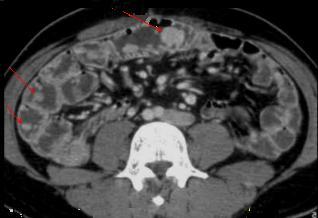

Petit lipome de

l'intestin ( fleche rouge ) . Aspect TDM

arrondie pedicule a hypo-dense endoluminale de

intestin a la region fosse iliaque gauche |